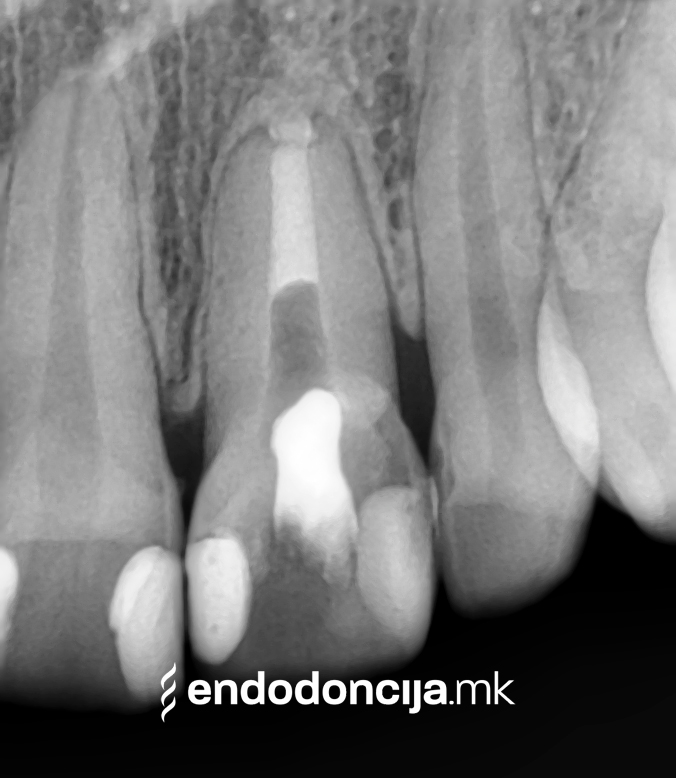

За време на претходните третмани, забот не само што бил ослабен со механички третман на коренскиот канал, туку и со поставување и закотвување на забното колче. Кога се ревидира третманот со коренскиот канал, овие колчиња треба да се отстранат колку што е можно повнимателно за да се задржи важната забна супстанција.

Она што е импресивно е прецизноста на микроскопските третмани. Дури и кога каналите се потешко достапни, може да се лоцираат и исчистат така што релапсите се со помала веројатност. Спротивно на тоа, скриените канали често остануваат неоткриени во конвенционалниот третман на коренскиот канал и затоа не можат да се чистат. Бактериите можат да се размножуваат таму без пречки и да предизвикаат воспаленија. Ова често останува незабележано со години додека не се појави забоболка, а со тоа и компликации.

Употребата на микроскоп исто така овозможува детектирање пукнатини или фрактури што може да предизвикаат болка или воспаление.